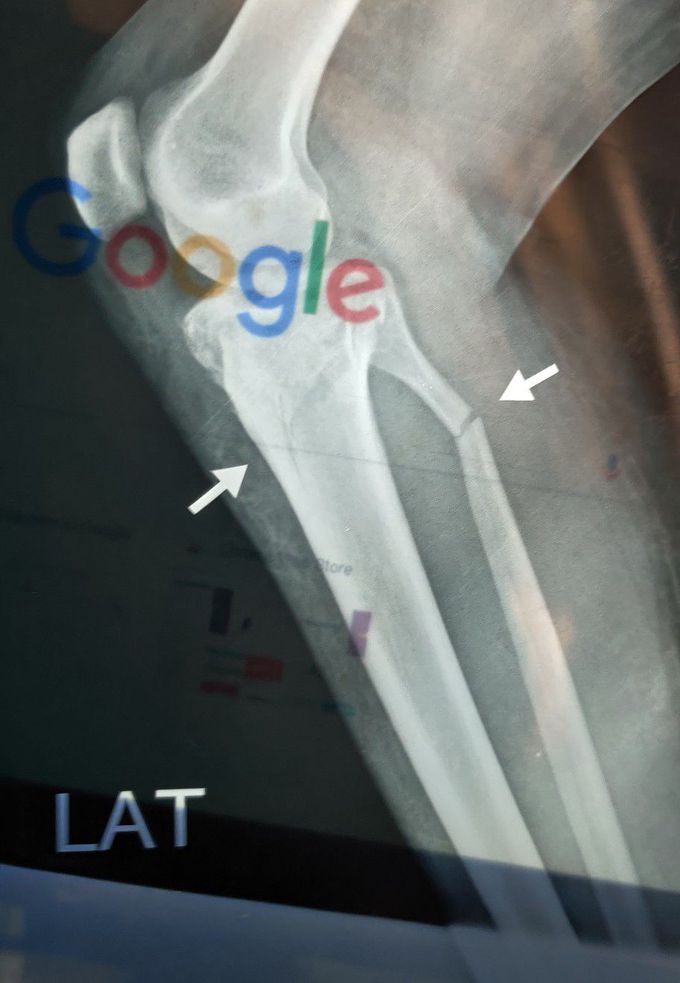

Tibia + Fibula Fracture

Fracture

Tibia

Fibula